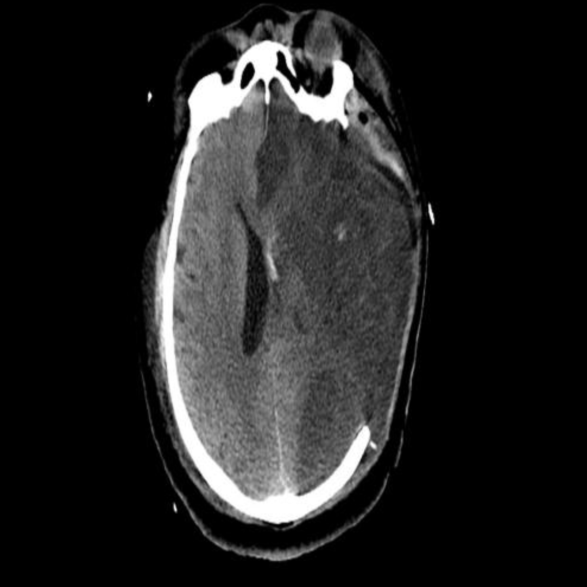

完善颅脑磁共振:

2.MRA示左侧颈内末端以远不显影。

术前MRA